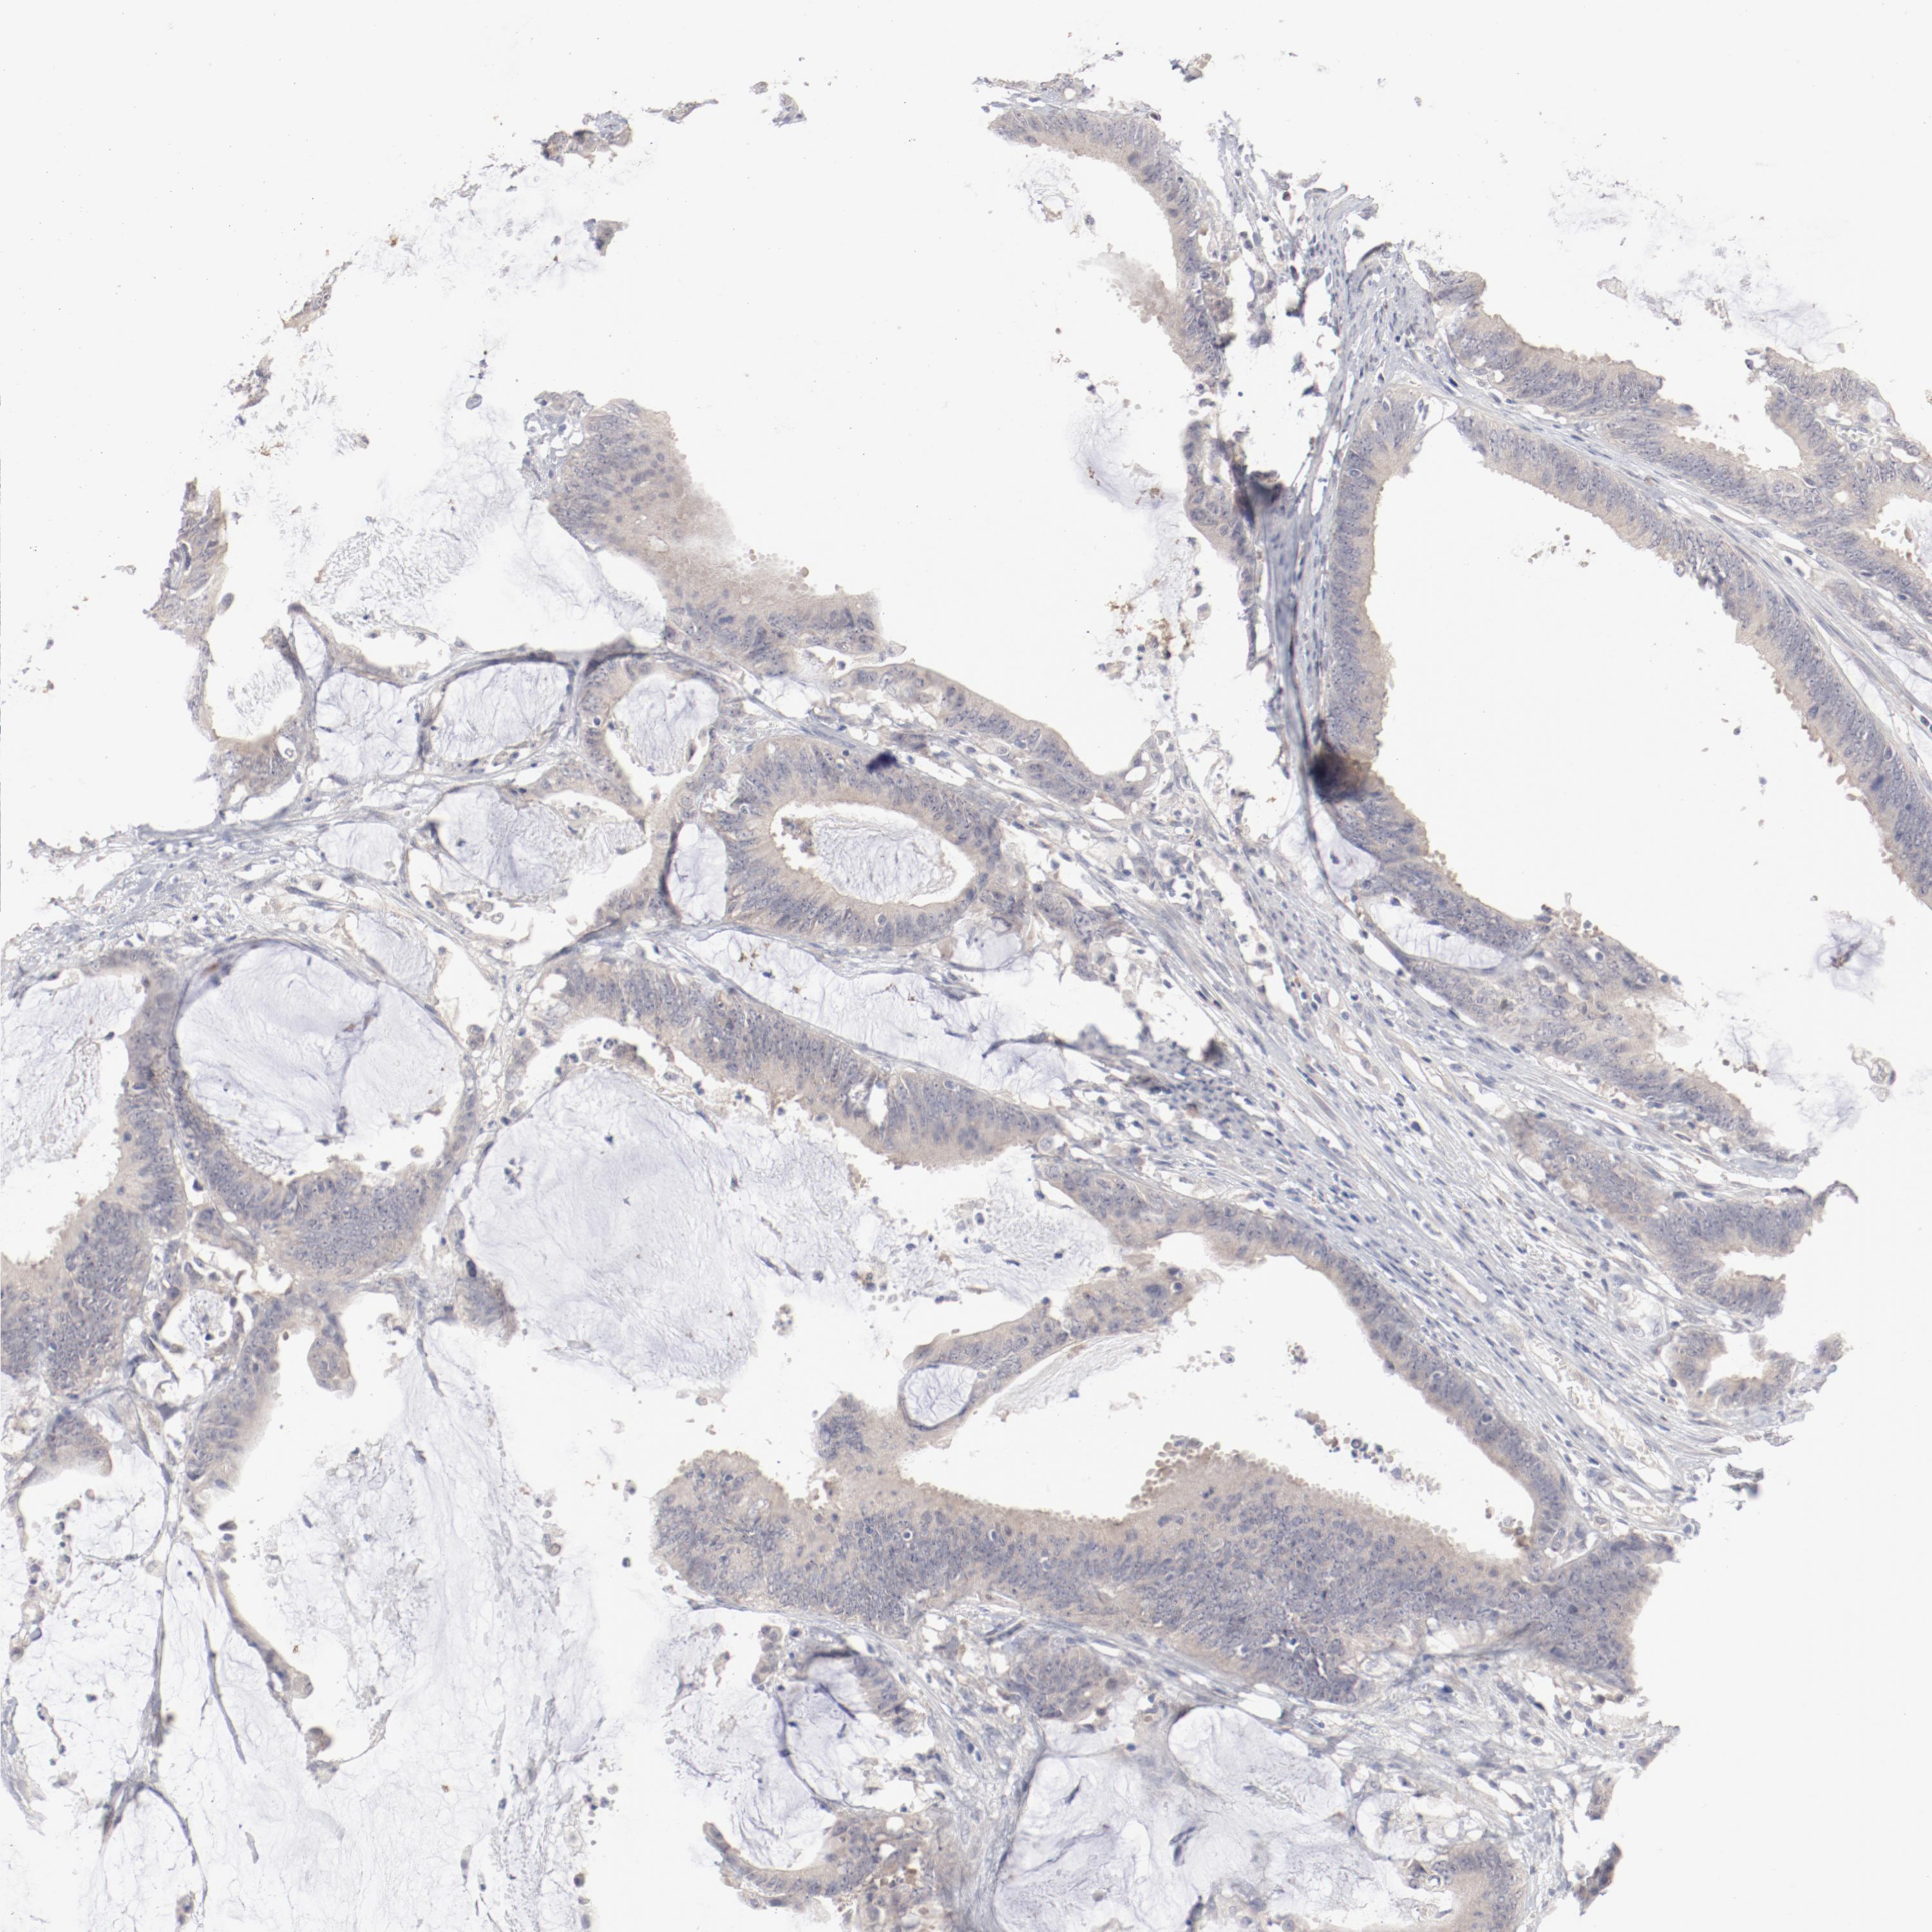

ANTIBODIES

AND

VALIDATION

Dictionary

Colorectal cancer

Human cancer